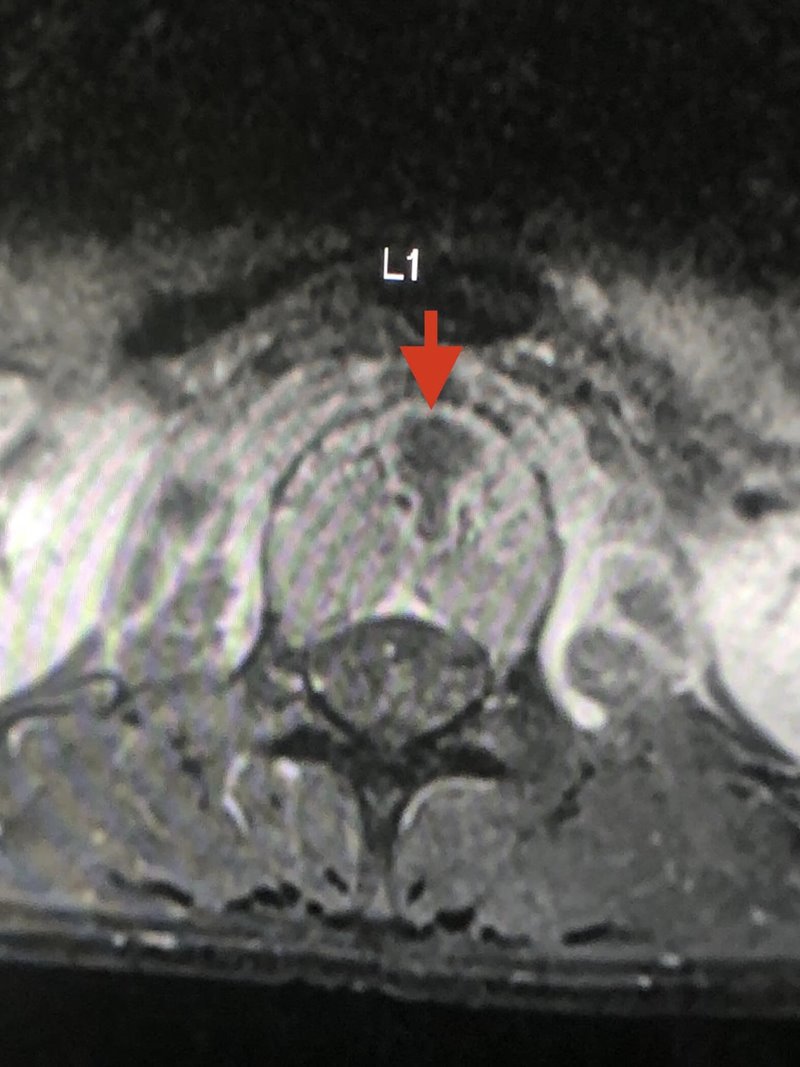

อย่างไรก็ตาม เมื่อลองทำ MRI กระดูกสันหลังส่วนเอว กลับพบความผิดปกติ และมีความเป็นไปได้ที่เธอจะเป็นวัณโรคของกระดูกสันหลังส่วนเอวชิ้นที่ 1 และสงสัยว่าจะมีการอักเสบรอบ ๆ เนื้อเยื่อกระดูกสันหลังส่วนเอวชิ้นที่ 1 และ 2 ร่วมด้วย จึงทำการเจาะเนื้อเยื่อรอบกระดูกสันหลัง ส่งตรวจย้อมเพื่อหาเชื้อวัณโรค และให้ผลลบ จากนั้นก็รอเพาะเชื้อวัณโรค ส่งตรวจพยาธิวิทยา พบว่าเนื้อเยื่อตายและไม่พบมะเร็ง และสรุปได้ว่า เธอเป็นวัณโรคที่กระดูกสันหลัง

ภาพจาก เฟซบุ๊ก หมอมนูญ ลีเชวงวงศ์ FC